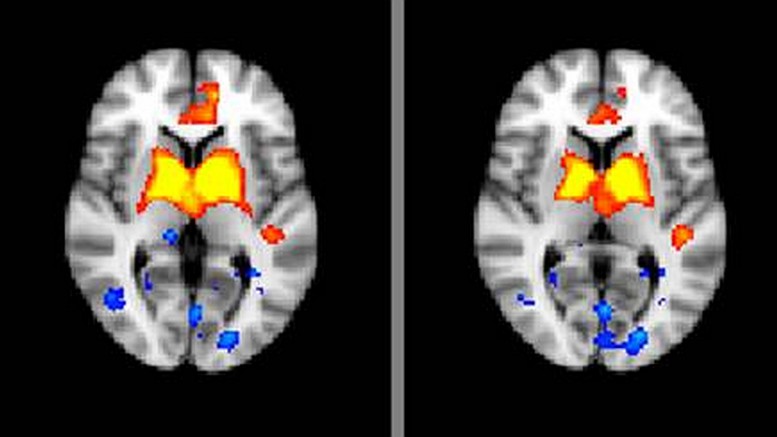

As opposed to traditional magnetic-resonance imaging, which gives detailed snapshots of the brain’s physical structure, fMRIs – for “functional” MRI – illustrate the parts of the brain that are receiving oxygen or are otherwise active. “This gives us a better idea how the structures are functioning and what sort of activity is going on within them,” Sarpal noted.

Researchers scanned schizophrenia patients in a resting state – lying still with their eyes closed for five minutes, substantially reducing brain functions – to create the baseline. Sarpal and his team focused specifically on the striatum, a central region of the brain often implicated in schizophrenia cases.